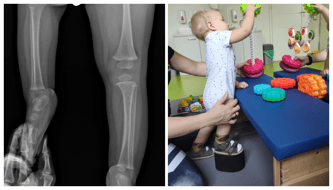

Gdy Filipek przyszedł na świat, jego prawa nóżka była już krótsza a około 4 cm. Dziś, gdy ma 15 miesięcy różnica powiększyła się do 10 cm!!!

Widzimy z jaką determinacją nasz kochany maluch próbuje stanąć przy kanapie, stoliku... Widzimy jego upadki, ale za chwilę wstaje i próbuję kolejny raz! To właśnie Filipek daje nam siłę, motywację i wiarę w to, że warto! Że naprawdę musimy zawalczyć o jego pełno sprawność! Mimo tylu przeciwności pozostaje on wiecznie uśmiechniętym chłopcem. Jego uśmiech zaraża i dodaje otuchy! Aby nie doszło do nienaturalnego wygięcia ciała, wytrwale ćwiczymy kręgosłup oraz obciążamy prawą nóżkę.

Niestety bez udziału licznych operacji jego nóżka może być krótsza o nawet 30 cm! Nie możemy do tego dopuścić! Musimy walczyć o sprawność naszego synka!

Dzięki ogromnemu wsparciu z Waszej strony udało nam się uzbierać pieniądze na pierwszą operację SUPERHIP i SUPERKNEE. Czyli na rekonstrukcji stawu biodrowego mającego na celu odtworzyć anatomię biodra oraz przygotować kość udową do wydłużania.

Chcemy uzbierać pieniądze potrzebne do opłacenia drugiej zaplanowanej operacji Filipka, czyli do pierwszego wydłużenia kości udowej założeniem zewnętrznego aparatu monolateralnego celem wydłużenia 8 cm. Wydłużanie zaplanowano na rok po pierwszej operacji z jednoczesnym usunięciem zespolenia wewnętrznego.